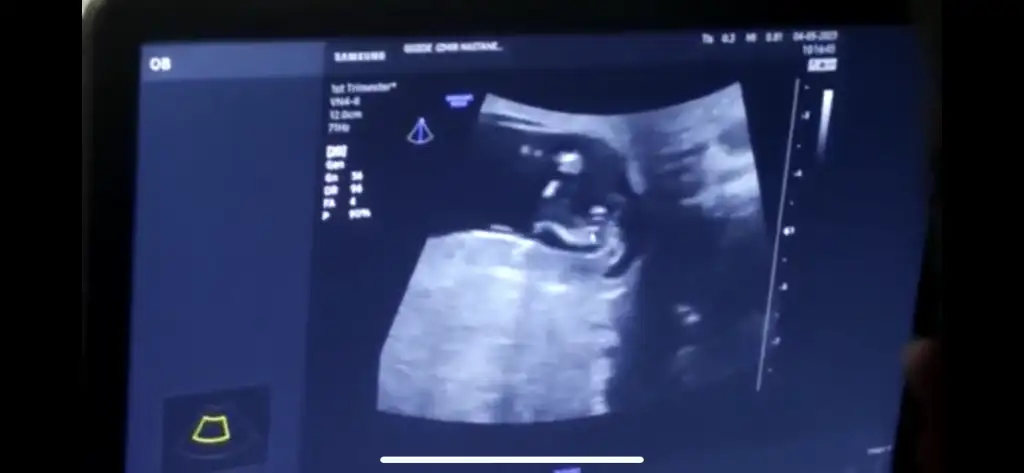

Ok işaretinin üstündeki çıkıntıyı gösterdi canım doktor o an kapattığı için çekemedi doktor, orası çıkıntı belli oluyor aslında ama

Bir de bu var canım nub’un göründüğü detaylıca

Yok canım en net görüntüleri attım zaten başka da görüntü vermediler. %80 erkek dedi kız olma ihtimali düşük o da bazen organ bölgesi ödemli olabiliyor ama büyük ihtimalle erkek dedi, zaten kızlarda genelde 3 çizgi oluyormuş sanırım sonradan duydum ben de bizde çizgi falan yok dikkatlice bakınca